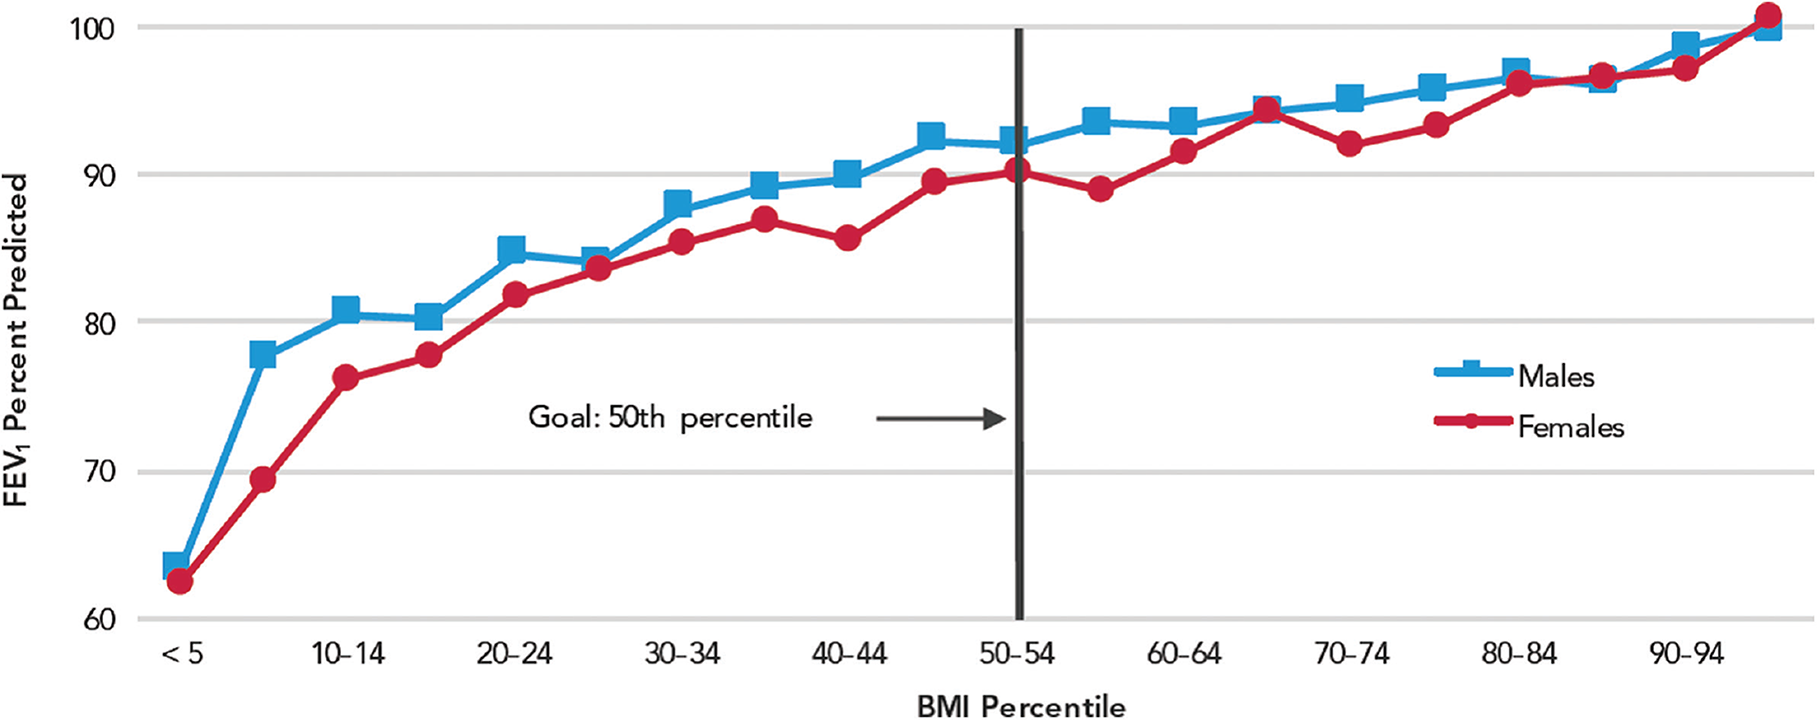

Pediatrics: Cystic Fibrosis in Childhood and Adolescence